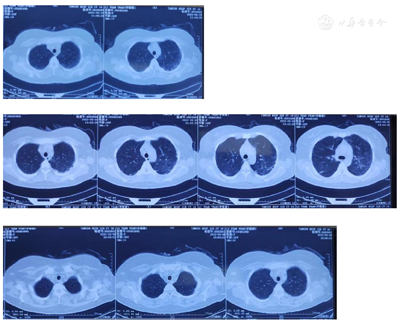

辅助检查:入院化验血常规:白细胞计数8.89×109/L,LYM 0.69×109/L,血红蛋白80 g/L,PLT 77×109/L,尿常规:尿蛋白1+,PCT 0.90 ng/ml,hs-CRP 4.13 mg/L,红细胞沉降率28.0 mm/h,IL-6 8.73 pg/ml,FRT>2 000 μg/L。生化指标:ALB 28.7 g/L,ALT 130 U/L,AST 67 U/L,BUN 62.03 mmol/L,肌酐226.9 μmol/L,GGT 49 U/L,UA 768.4 μmol/L,a-HBDH 1 120 U/L,LDH 1 506 U/L,TC 5.61 mmol/L,TG 3.03 mmol/L。Fib 1.730 g/L,便常规、抗链0、免疫球蛋白补体系列正常范围,血小板抗体、RF、免疫固定电泳、ANCA系列、自免肝抗体、自身抗体谱、aCLs、抗CCP、RF亚型、RA33、抗人球蛋白试验、T-Spot阴性。ADAMTS13酶活性及抑制性抗体检测:ADAMTS13活性69. 03%,ADAMTS13活性抑制性抗体阴性,NK细胞活性:15. 80%,sCD25 4713pg/ml。心电图:窦性心律,频发室性早搏。心脏彩超:二维超声心动图大致正常,多普勒超声心动图大致正常,肺动脉收缩压23 mmHg。胸部CT:(1)右肺中叶、双肺下叶索条灶,双侧胸膜腔少量积液;(2)心腔密度减低。腹部+浅表淋巴结彩超:胆囊大小正常,胆囊壁胆固醇结晶析出,双肾大,双肾弥漫性改变,请结合肾功能检查;轻度肾积水,双侧输尿管未见扩张,膀胱区未见明确异常,腹腔积液(少量),肝、胰、脾、子宫大小正常,图像未见异常,双侧附件区未见明确异常,双侧颈部、锁骨上窝、腋窝、腹股沟区未见明确肿大淋巴结,双侧胸腔无积液。

2022年4月5日,患者发热,体温最高38.7℃,有流涕,无咽痛,无畏寒寒战,无皮疹、关节肿痛,查血常规:白细胞计数8.95×109/L,LYM 0.53×109/L,NEU 8.09×109/L,PLT 140×109/L,RBC 2.36×1012/L,血红蛋白70 g/L;红细胞沉降率22.0 mm/h,PCT 0.51 ng/ml,hs-CRP 13.60 mg/L,FRT 14 940 μg/L。生化指标:TG 2.04 mmol/L,UA 596.0 μmol/L,肌酐82.0 μmol/L,BUN 22. 1 mmol/L,ALT 124 U/L,AST 82 U/L,a-HBDH 781 U/L,LDH 998 U/L,Fib 2.6 g/L,调整甲泼尼龙片早24 mg,晚16 mg,蓝清感冒颗粒、盐酸莫西沙星口服。2022年4月8日,患者仍有发热,体温最高39.6℃,血常规:白细胞计数7.67×109/L,LYM 1.04×109/L,NEU 7.21×109/L,PLT 111×109/L,血红蛋白74 g/L,骨髓穿刺:骨髓增生极度活跃,结合病史。骨髓活检:取材偏少,粒系、红系均可见,巨核细胞不少,可见部分淋巴细胞。给予甲强龙40 mg,2次/d静脉滴注、丙种球蛋白20 g冲击5 d、注射用头孢哌酮钠舒巴坦钠3.0 g,2次/d。2022年4月10日,患者间断低热,37.5℃,查血常规:白细胞计数3.11×109/L,LYM 0.79×109/L,PLT 97×109/L,血红蛋白66 g/L,hs-CRP 4.80 mg/L,FRT 17 294 μg/L,Fib 2.2 g/L,生化指标:a-HBDH 641 U/L,LDH 946 U/L,ALT 488 U/L,AST 259 U/L,TG 1.76 mmol/L。2022年4月12日给予甲强龙500 mg冲击3 d后甲强龙40 mg/d,3 d未发热,第4天晨测体温38℃,生化指标:GGT 63 U/L,ALT 324 U/L,AST 96 U/L;血常规:白细胞计数3.34×109/L,LYM 0.79×109/L,PLT 68×109/L,RBC 3.25×1012/L,血红蛋白96 g/L,Fib 1.400 g/L,FRT 11 262 μg/L。2022年4月15日给予依托泊苷150 mg,2次/周,输注,加用甲泼尼龙片晚16 mg口服,血常规:白细胞计数3.22×109/L,PLT 69×109/L,血红蛋白90 g/L,未发热。2022年4月21日激素调整为甲泼尼龙片早32 mg、晚16 mg口服,Fib 2.240 g/L,生化指标:ALT 67 U/L,a–HBDH 366 U/L,LDH 448 U/L,血常规:白细胞计数3.30×109/L,LYM 0.54×109/L,PLT 79×109/L,血红蛋白90 g/L ,红细胞沉降率27.0 mm/h,hs-CRP 3.83 mg/L,FRT 9 569 μg/L,IL-6正常,未发热。2022年4月24日激素减量为甲泼尼龙片早32 mg、晚8 mg口服。2022年4月27日,患者体温升高37.6℃,激素调整为甲泼尼龙片早24 mg、晚16 mg口服,回报粒缺,2022年4月28日~4月29日升至39.9℃,查血常规:白细胞计数3.24×109/L,LYM 0.75×109/L,PLT 130×109/L,血红蛋白70 g/L,尿常规:尿蛋白1+ g/L,红细胞沉降率53.0 mm/h,hs-CRP 83.70mg/L,FRT 6 302 μg/L,生化指标:a-HBDH 200 U/L,LDH 256 U/L,T-Spot、EBV-DNA、HCMV-DNA均阴性,二代基因测序(血):人多瘤病毒1型(BK多瘤病毒),序列数21;人类疱疹病毒1型,序列数16,胸部CT:双肺间质增生伴炎症。给予地塞米松磷酸钠注射液10 mg,2次/日、胸腺法新提高免疫、丙球5g、血浆置换控制病情,停用环孢素,给予盐酸万古霉素、美罗培南、伏立康唑、复方新诺明抗感染(图1)。2022年5月1日起未再发热,2022年5月7日查血常规:白细胞计数26.82×109/L,PLT 133×109/L,血红蛋白70 g/L,调整激素为地塞米松磷酸钠注射液早10 mg,晚甲泼尼龙片16 mg。2022年5月9日查血常规:白细胞计数21.38×109/L,PLT 119×109/L,血红蛋白67 g/L,生化:ALT 93 U/L,AST 48 U/L,a-HBDH 394 U/L,LDH 560 U/L,Fib 1.2 g/L,hs-CRP 6.70 mg/L,红细胞沉降率18 mm/h,FRT 2 832μg/L,胸部CT:与2022年5月3日比,双肺炎症伴间质增生较前有所缩小,调整激素,早甲强龙40 mg,晚甲泼尼龙片16 mg,他克莫司胶囊早2 mg,晚1 mg,停用抗生素,伏立康唑、SMZ减至预防量。2022年5月12日查血常规:白细胞计数17.07×109/L,PLT 112×109/L,血红蛋白82 g/L,生化指标:ALT 73 U/L,a-HBDH 311 U/L,LDH 403 U/L,凝血系列正常,FRT 1 199 μg/L,甲泼尼龙片早32 mg、晚16 mg,给予托珠单抗注射液400 mg控制原发病,5 d后复查肝功转氨酶5倍升高,考虑托珠单抗不良反应,予停用,换用巴瑞替尼片2 mg/d口服控制病情。